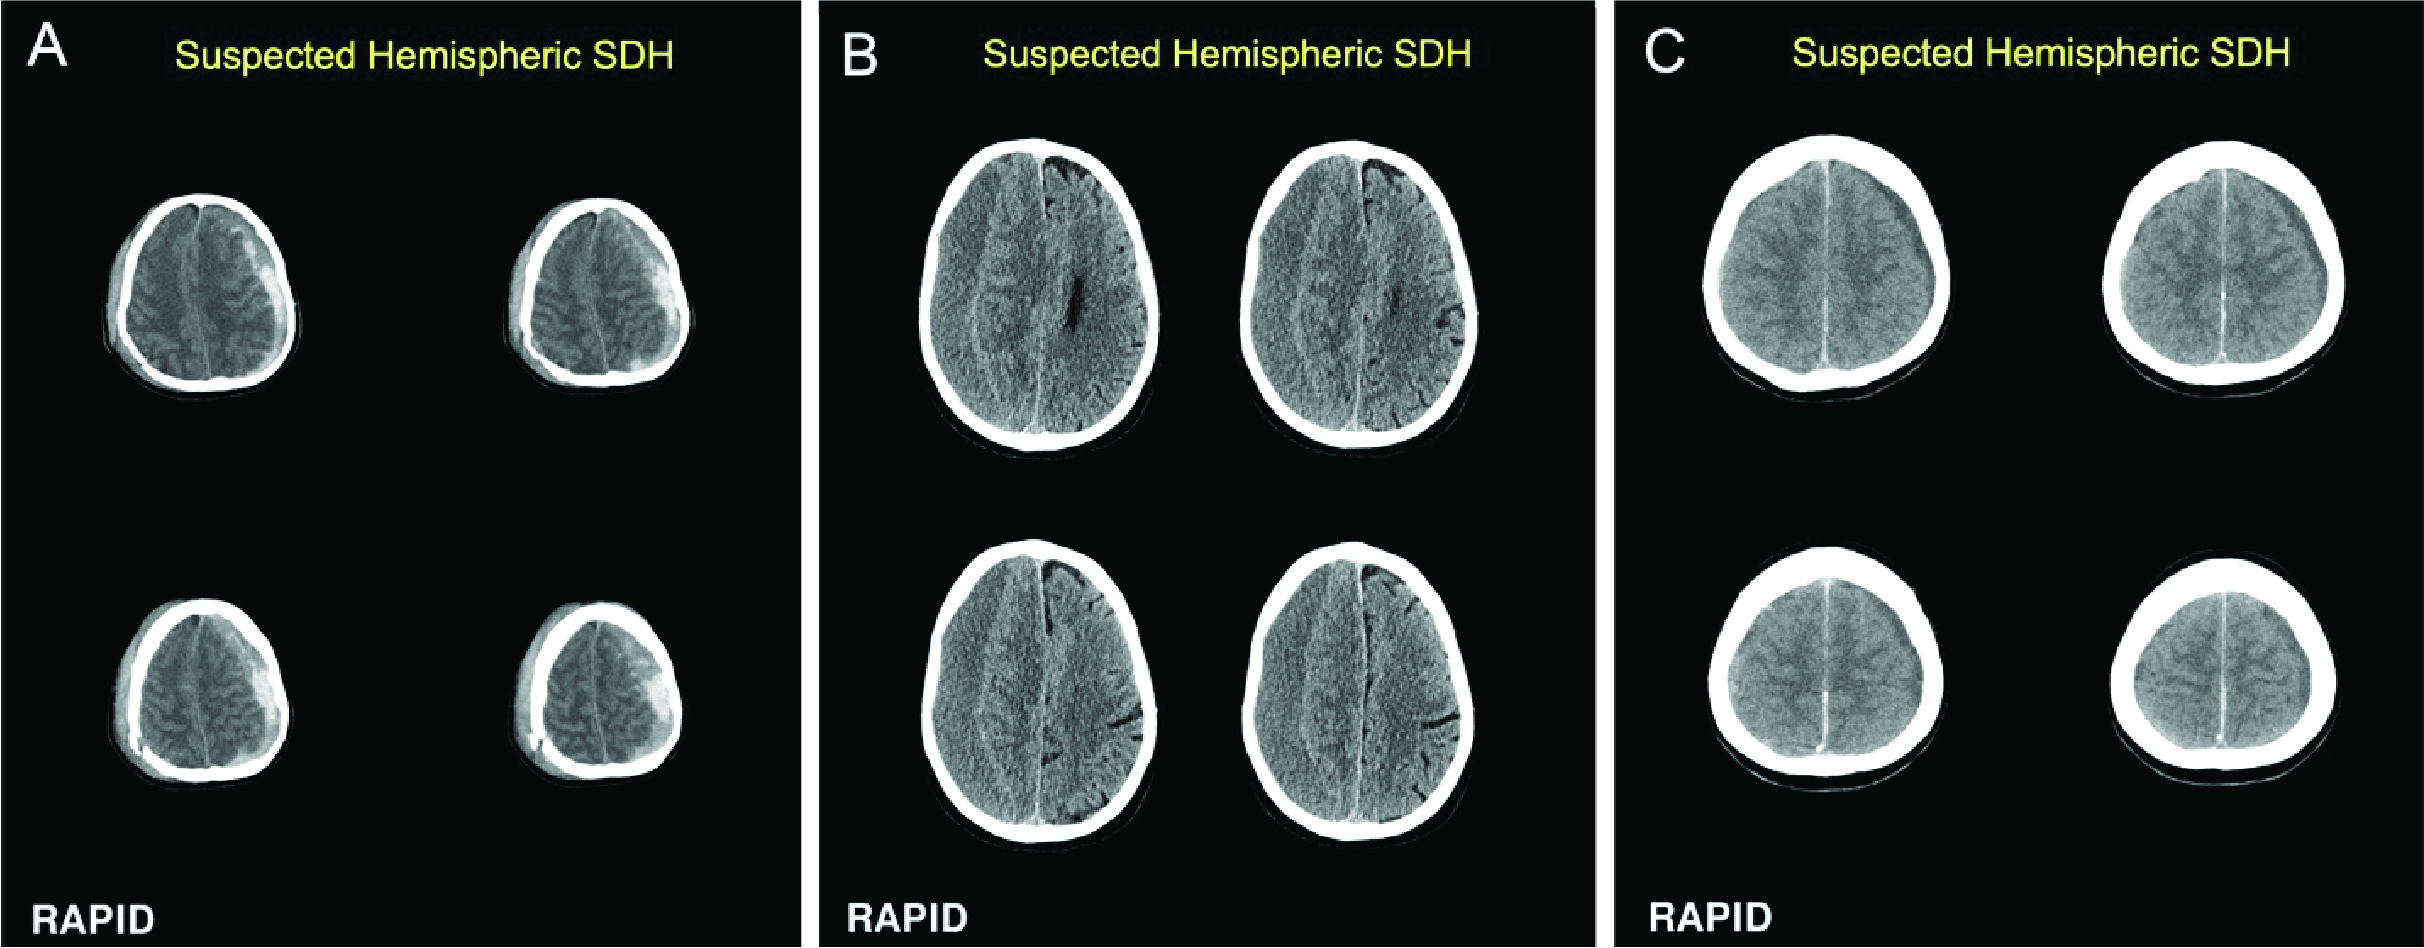

Abstract Body: Introduction: Subdural hematomas (SDHs) are increasing in prevalence and are one of the most common pathologic processes necessitating neurosurgical intervention. Acute SDHs may require urgent surgery and detection of chronic SDHs is of increasing importance due to recent data demonstrating successful management with middle meningeal artery embolization. The prognosis for SDH patients varies significantly based on the hematoma's size, the patient's age, and the promptness of treatment. Rapid SDH is a fully automated software with FDA clearance for triage and notification of hemispheric SDH from non-enhanced head CT (NCCT) images. We determined the accuracy of Rapid SDH for both acute and chronic SDH compared to gold standard expert readers.

Results: A total of 313 cases, including a consecutive series of patients that was enriched for SDH, were identified (mean age, 63 years ± SD 22; 189 male, 111 female, 13 unknown). Three cases were excluded from the analysis (one for volume <1 ml, two for scan quality). Of the 310 remaining, 157 were positive for SDH (48 acute, 47 chronic, 44 mixed, and 18 isodense) and 153 were negative for SDH per consensus of 3 expert neuroradiologists. Performance of the software, based on the neuroradiologist gold standard, demonstrated a sensitivity of 92.4% (95% CI: 87.1, 95.6) and a specificity of 98.7% (95% CI: 95.4, 99.6) for the detection of SDH. The sensitivity for chronic SDH (91.5% 95% CI 80.1-0.96.6) did not differ from acute/subacute SDH (92.7% CI 86.3-0.96.3). The median processing time was approximately 45 seconds.

Conclusion: The results confirm that automated imaging analysis using Rapid SDH provides fast and accurate detection of both acute and chronic SDH on NCCT. Use of this software has the potential to expedite SDH diagnosis and treatment.